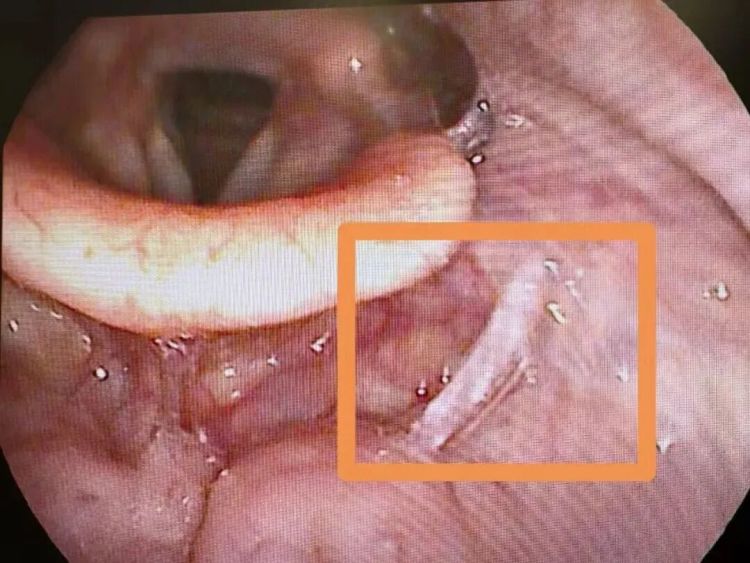

万幸的是,过程郭医师的专科科罚,到手将带血的碎骨取出,小文终于能大口呼吸了,此时的他睫毛上还挂着未干的眼泪。“汤饭里的碎骨、鱼刺一定要仔细挑,孩子吃饭千万要小心!”郭医师指着托盘里的碎骨,向小文姆妈注重嘱托谈。

郭医师先容,因误食碎骨、鱼刺等导致喉部异物,进而激发不适甚而损害的情况,在临床上并不稀有,尤其在食用“汤泡饭”时更容易发生。

近一个月,萧山区一病院急诊接诊的相干病东谈主就有800余例。其中,大部分患者的异物位置较浅,可通过异物钳平直取出,但也不乏因异物卡得深、面目罕见,需借助软镜材干取出的案例,斗鱼体育app不仅颐养周期长,患者承受的祸殃也更多。

第一时刻就医:若异物感热烈、陪伴难受或吞咽坚苦,不要徜徉,立即前去病院耳鼻咽喉科急诊。医师可通过喉镜快速安全取出异物,拖延可能导致感染、喉部穿孔等严重恶果。